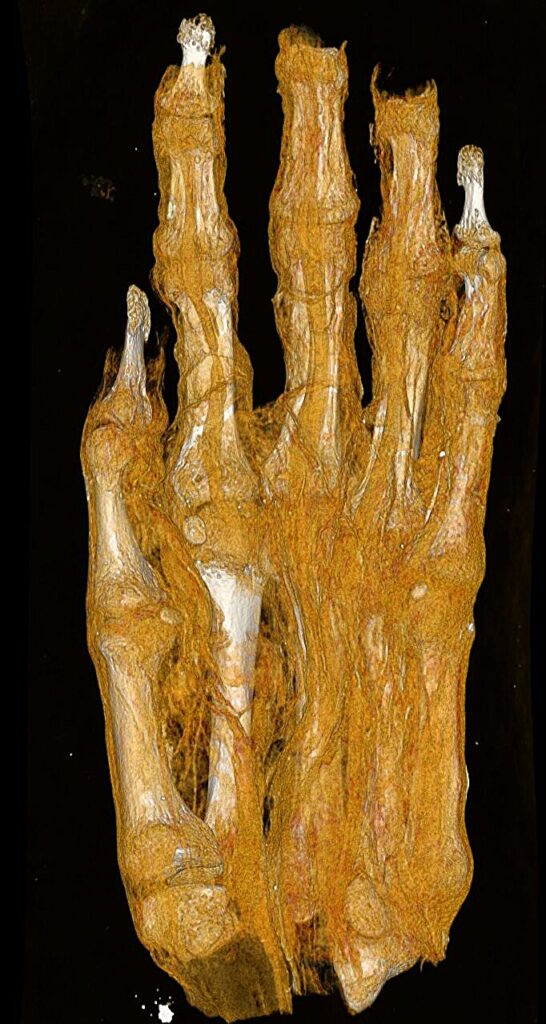

One of the most remarkable aspects of the new imaging project is its ability to correct long-standing historical misidentifications. In the world of archaeology, things are not always what they seem from the outside. One particular set of remains arrived at the museum identified only as a “mummy bundle.” Without the benefit of internal imaging, it was initially cataloged as a human head. Later, some hypothesized it might be the mummy of a bird.

It was only through CT technology that the truth emerged: the bundle actually contains a mummified adult foot. The new high-resolution scans are now going a step further, analyzing the distinct layers of the bandages wrapped around the limb. The images clearly show different structural characteristics within the textile remnants, which may provide clues about the specific mummification techniques used and whether the individual suffered from any identifiable illnesses. While researchers believe the foot was originally part of a complete mummy, the reason it was separated and the timing of that dissection remain mysteries that the team is still working to solve.